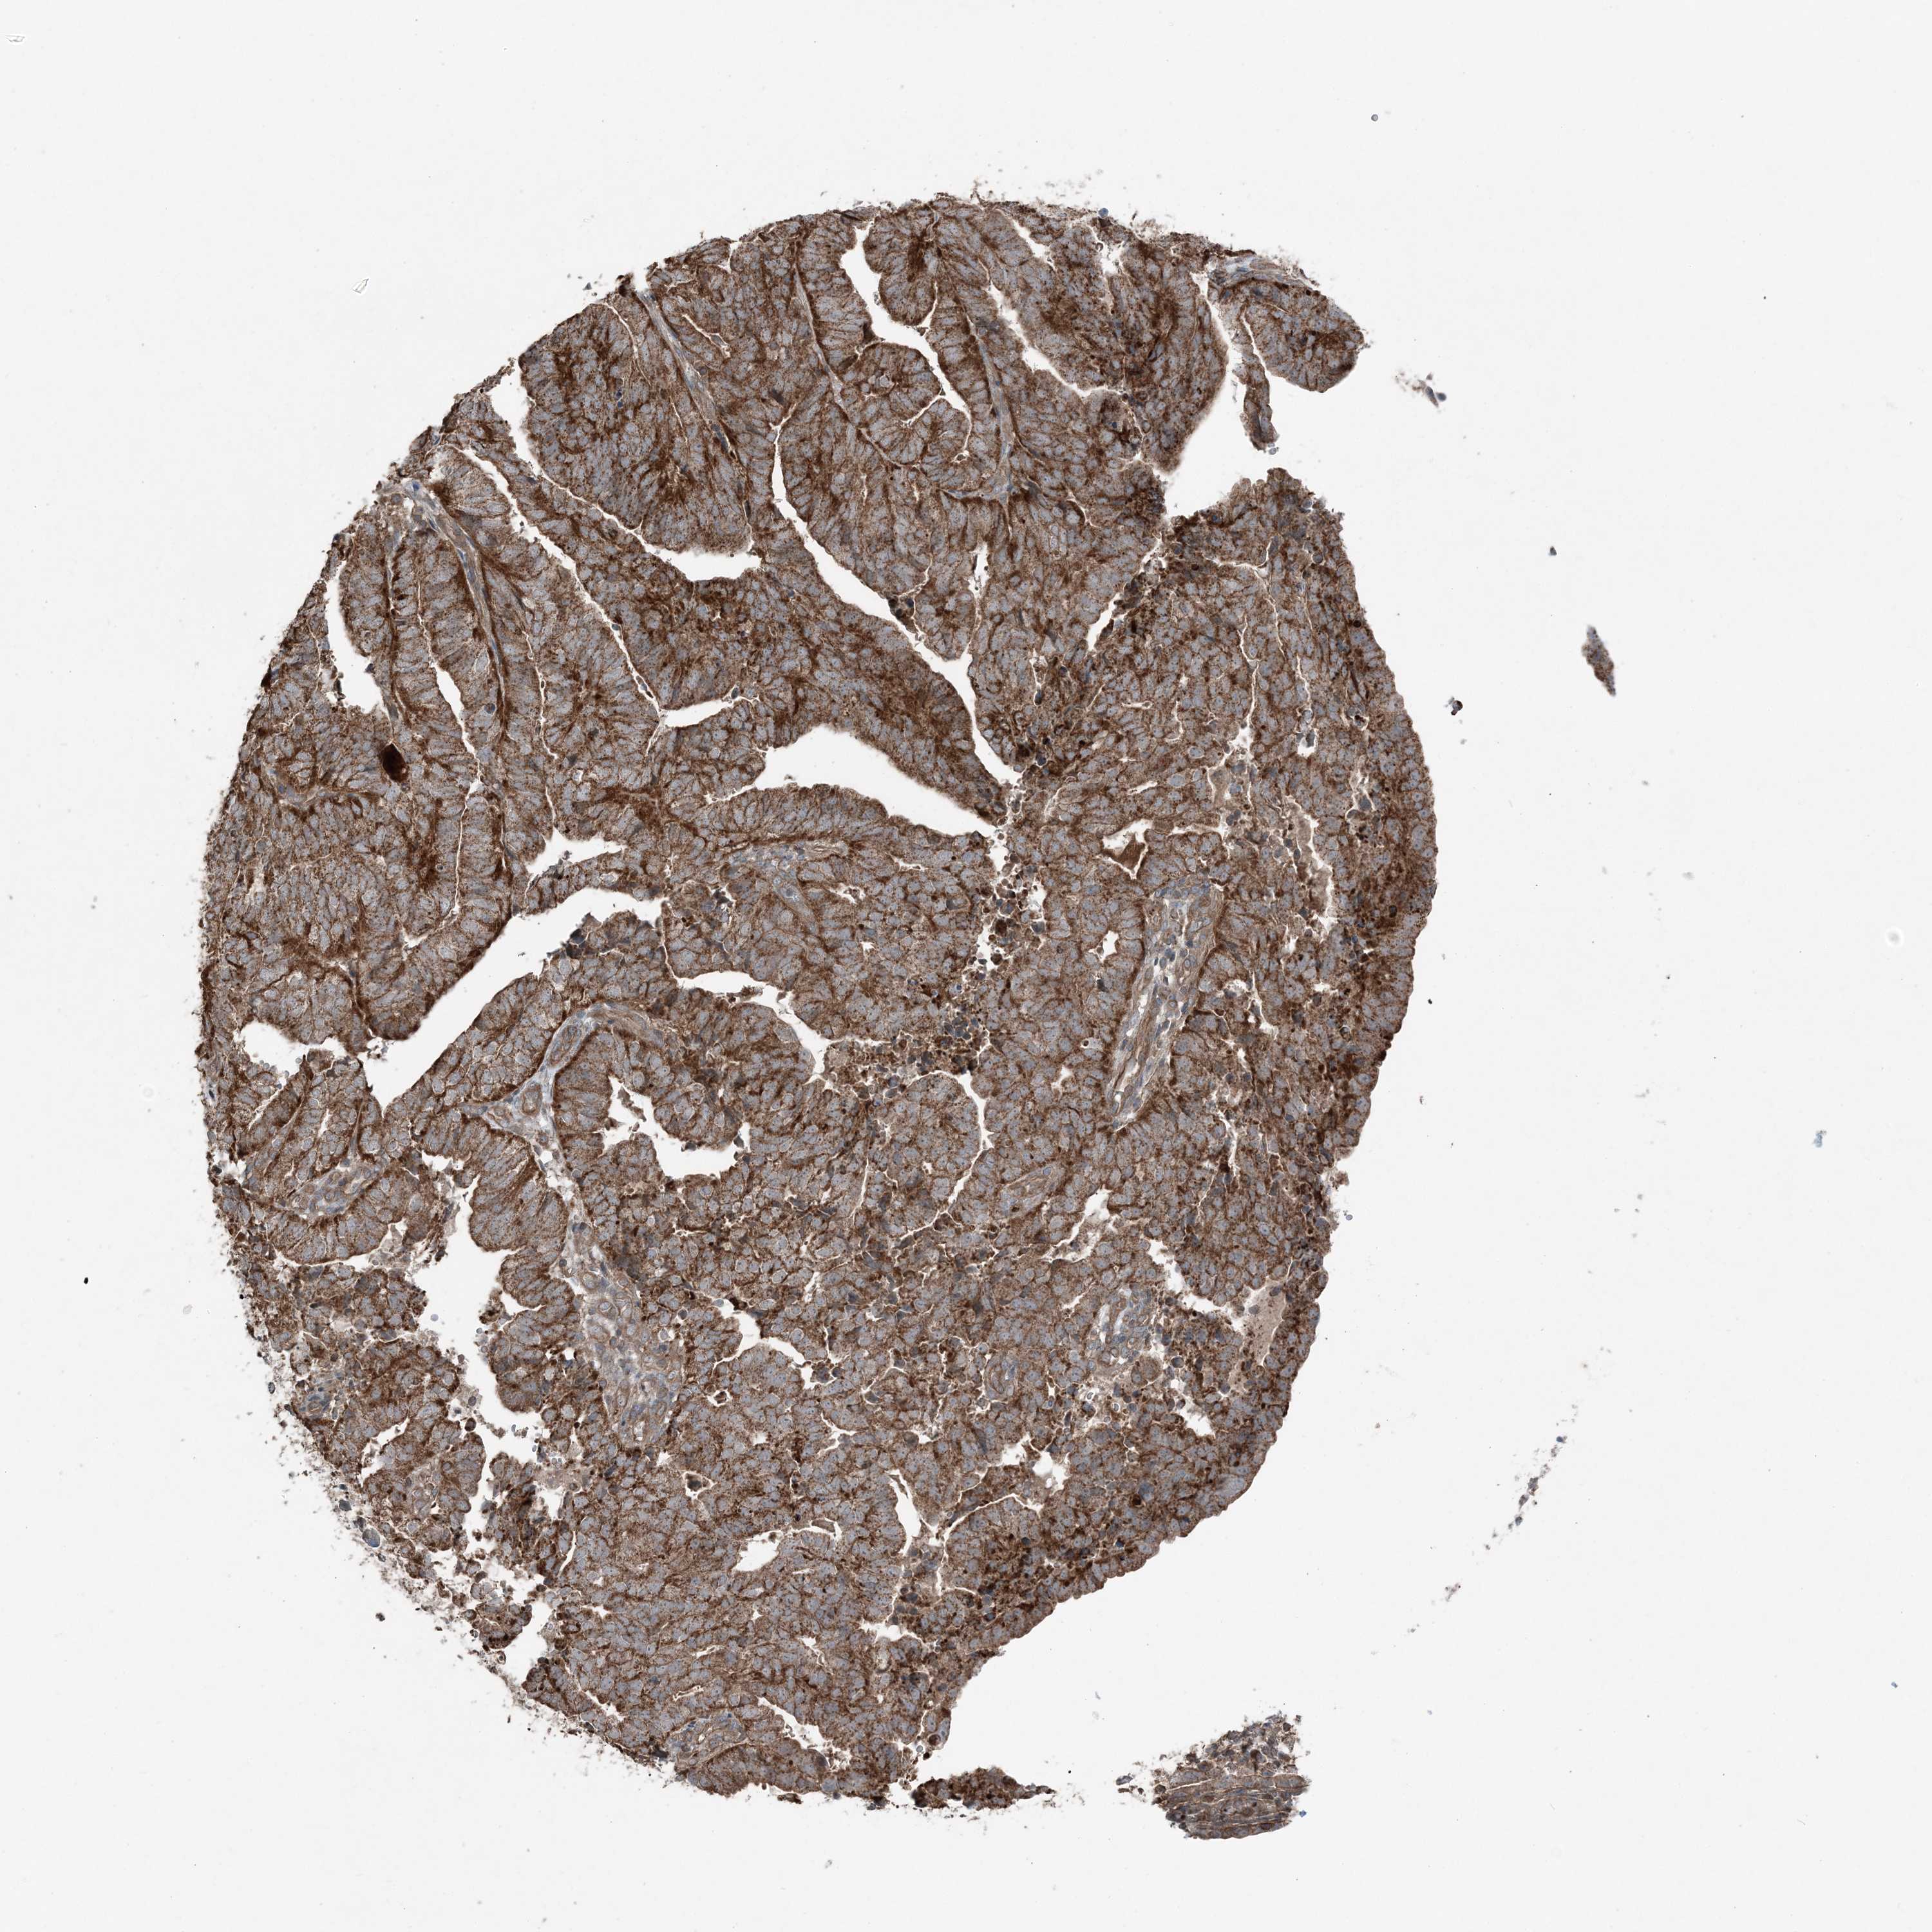

ENDOMETRIAL CANCER - Protein expressioni

A mouse-over function shows sample information and annotation data. Click on an image to view it in a full screen mode. Samples can be filtered based on level of antibody staining by selecting one or several of the following categories: high, medium, low and not detected. The assay and annotation is described here.

Note that samples used for immunohistochemistry by the Human Protein Atlas do not correspond to samples in the TCGA dataset.

Antibody stainingi

Antibody staining in the annotated cell types in the current human tissue is reported as not detected, low, medium, or high, based on conventional immunohistochemistry profiling in selected tissues. This score is based on the combination of the staining intensity and fraction of stained cells.

Each image is clickable and will lead to virtual microscopy that enables deeper exploration of all samples and also displays staining intensity scores, fraction scores and subcellular localization as well as patient and tissue information for each sample.

Antibody HPA036492

Antibody HPA036668

Staining

High

Medium

Low

Not detected

Intensity

Strong

Moderate

Weak

Negative

Quantity

>75%

75%-25%

<25%

None

Location

Nuclear

Cytoplasmic/membranous

Cytoplasmic/membranous,nuclear

Adenocarcinoma, NOS